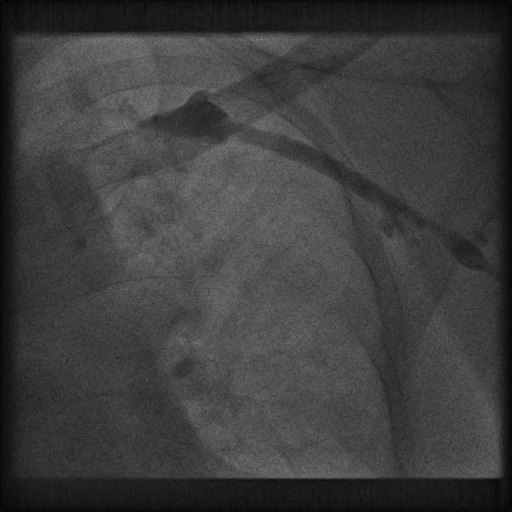

腋静脉造影

十级寻找CS

相对运动无法使鞘管深入CS

冒烟确认鞘管位置

● CS开口朝上,右房巨大,6250鞘管无法深入CS,从而无法稳定,且鞘管直接造影没法显示靶静脉情况,无法利用球囊造影,此时利用鞘中鞘,1、完成造影,2、提供支撑,为LV电极导线到达提供路径与支撑